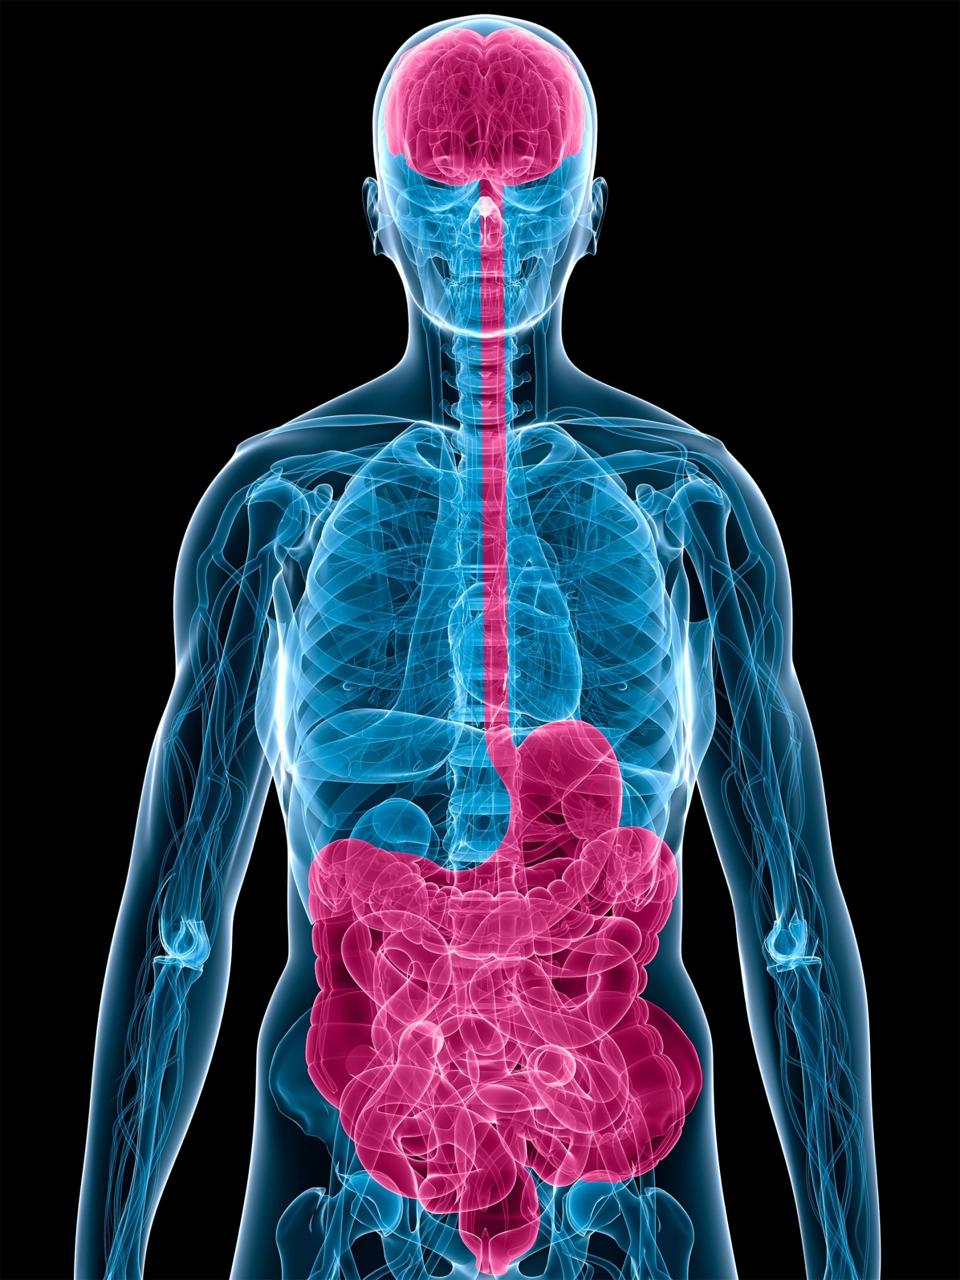

Diese Bereiche regulieren Emotionen und Stressantworten. Eine ausgewogene Darmflora, unterstützt durch Inulin, kann über die Darm-Hirn-Achse indirekt zu einem normalen emotionalen Gleichgewicht beitragen. Zusätzlich helfen antioxidative Substanzen wie Resveratrol und Quercetin, die Zellen vor oxidativem Stress zu schützen.

Der Darm beeinflusst das Gehirn maßgeblich über eine enge Verbindung, die Darm-Hirn-Achse. Inulin dient als präbiotischer Ballaststoff und trägt so zu einer gesunden Darmflora bei, was wiederum indirekt das allgemeine mentale Wohlbefinden unterstützen kann.